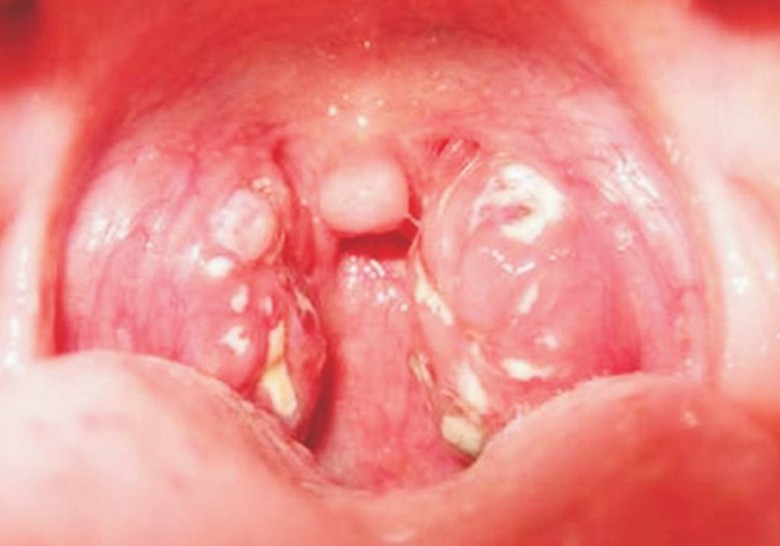

Bạch hầu là bệnh truyền nhiễm cấp tính, có tỷ lệ tử vong cao (Ảnh minh họa).

Trước đó, ngày 24/6, bệnh nhân C, có biểu hiện sốt, ho, đau họng, tự mua thuốc điều trị (thuốc tây và thuốc nam) nhưng không đỡ. Đến đêm 30/6, C nhập viện TTYT Kỳ Sơn với tình trạng mệt mỏi, da, niêm mạc kém hồng, sốt 37,8°C, ho, đau họng, khàn tiếng, sưng vùng cổ phải, nuốt đau, nổi hạch góc hàm 2 bên, amydal to có dịch mủ, có giả mạc trắng bám amydal và lưỡi gà, dễ bóc tách. Bệnh nhân được chẩn đoán mắc bệnh bạch hầu.

Biểu hiện bệnh có thể từ nhẹ đến nặng, thường có giả mạc màu trắng ở tuyến hạnh nhân, hầu họng, thanh quản, mũi, có thể xuất hiện ở da, các màng niêm mạc khác như kết mạc mắt hoặc bộ phận sinh dục. Biến chứng bệnh bạch hầu dễ gây suy hô hấp và tuần hoàn, liệt khẩu làm thay đổi giọng nói, sặc và khó nuốt khi ăn uống, lú lẫn. Nặng thì hôn mê, sau đó tử vong.